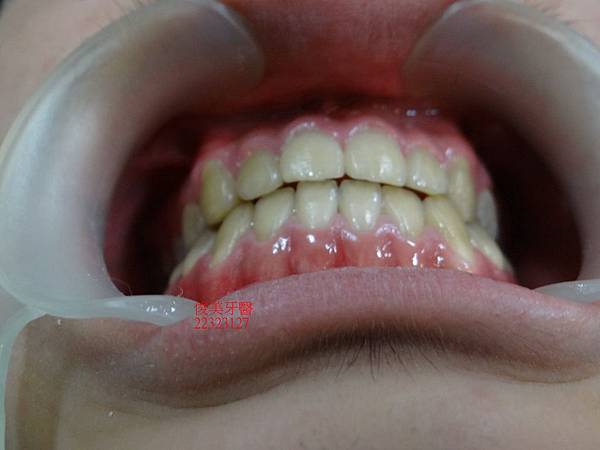

治療接近尾聲....

矯正器拆除了,患者非常開心,家長也很滿意,目前配戴維持器,定期檢查即可。

經上矯正器後,調整咬合...

採用不需做正顎手術,不拔牙方式做調整。

矯正結束後的狀況非常良好。